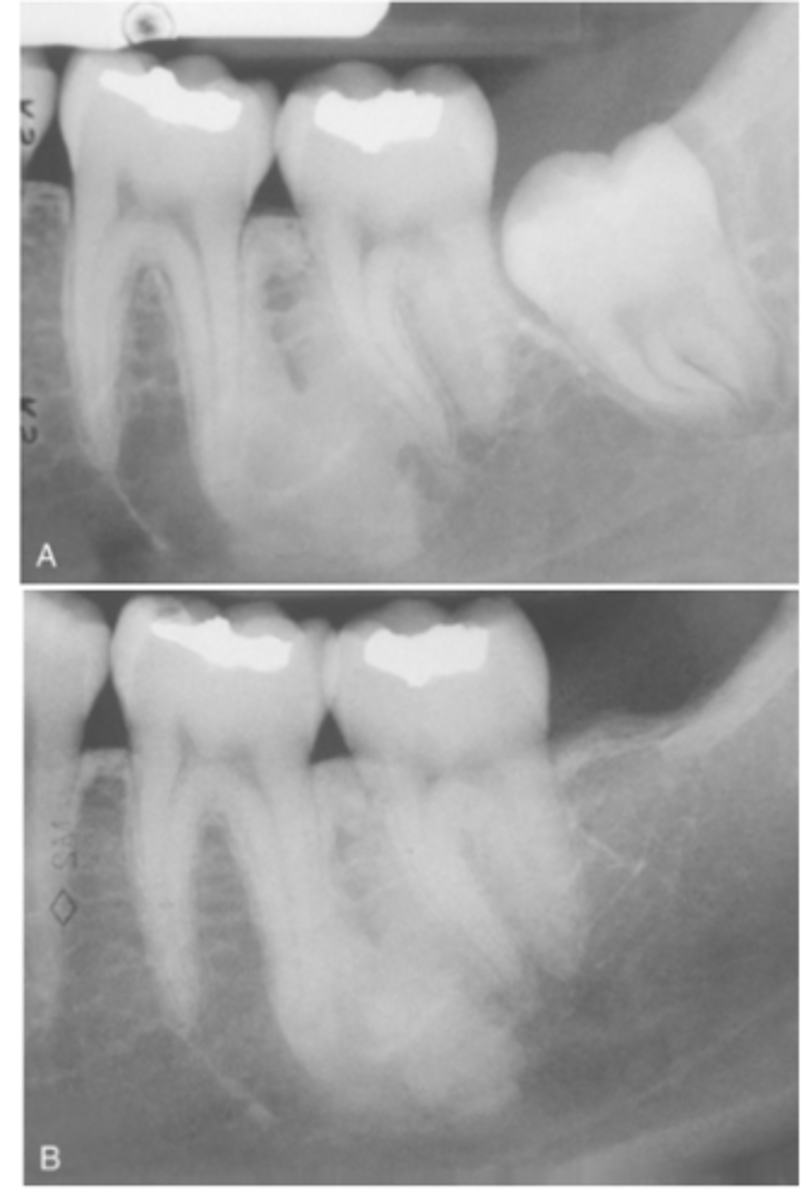

What do radiographic signs show in Idiopathic Osteosclerosis

Well-defined radiopacity

Most are associated to a root apex

What is the treatment for Idiopathic Osteosclerosis

Follow-up with radiographs if discovered during adolescence